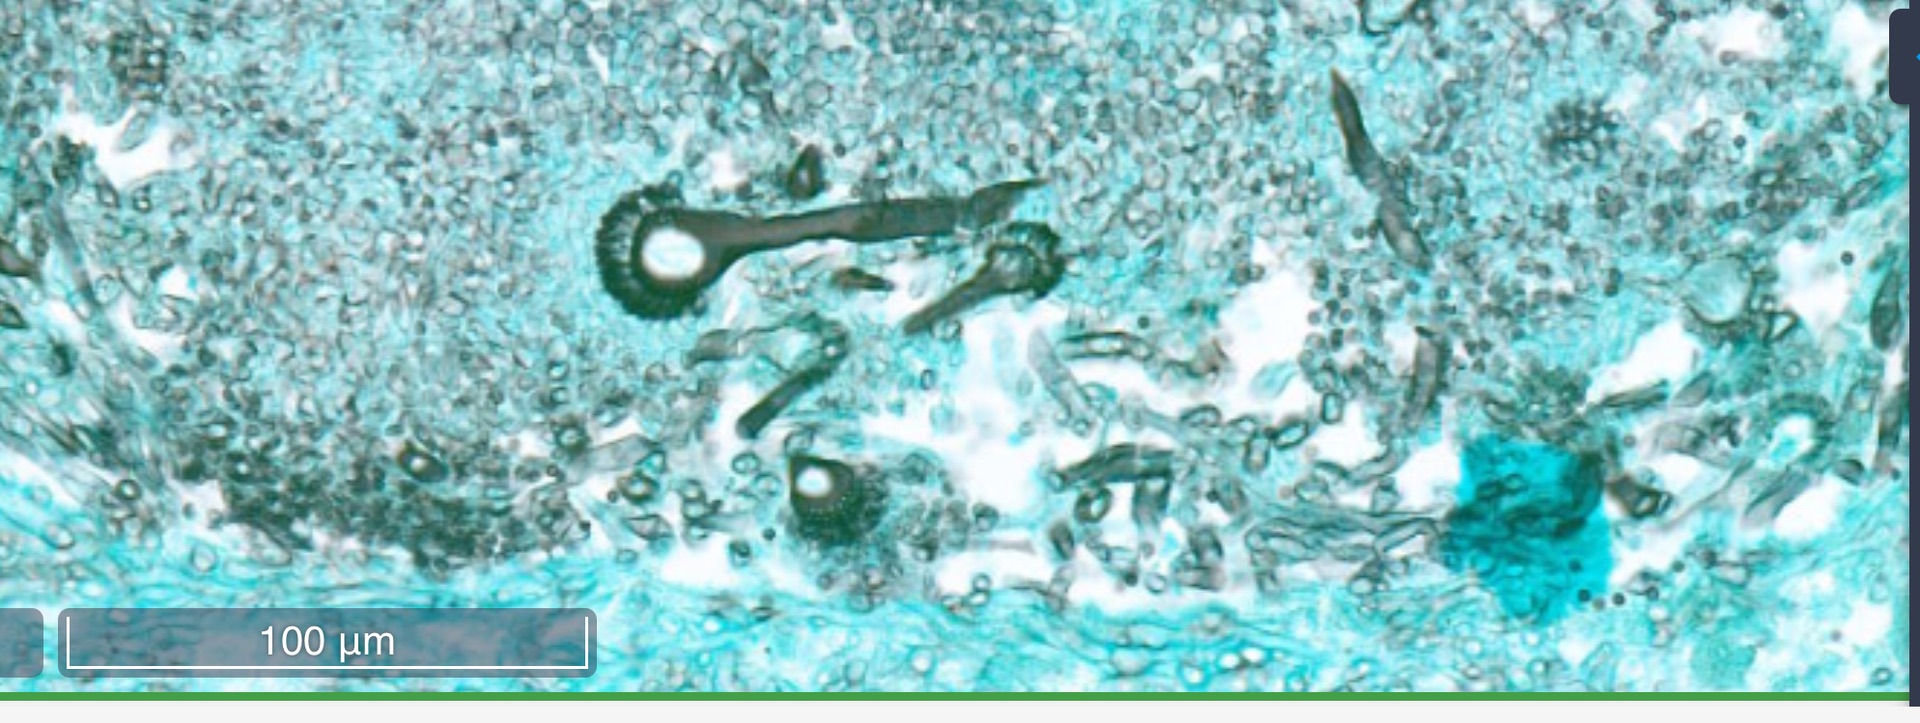

Aspergillose Lunge

Grocott Färbung

Hier besonders, Ausbildung von Konidien, welche sich im Schnitt als kleine Perückenköpfe zeigen.